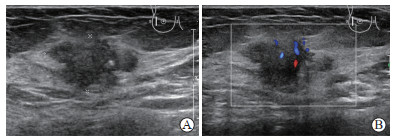

纳入单侧浸润性乳腺癌女性患者978例、超声图像4 414张。患者年龄22~97岁,平均年龄(56±12)岁。按照患者例数比6∶2∶2随机分为训练集、验证集和测试集,其中训练集587例(2 633张图)、验证集196例(904张图)、测试集195例(877张图),3组患者社会人口学信息和一般临床特征差异无统计学意义(均P>0.05,表 1)。在全部研究对象中,复发患者119例(12.17%),其中训练集71例、验证集23例、测试集25例。纳入病例的超声图像示例如图 1

图  1  纳入病例的超声图像示例

Fig.  1  Examples of ultrasound images of enrolled cases

A: Two-dimensional grayscale image; B: Color Doppler blood flow image.